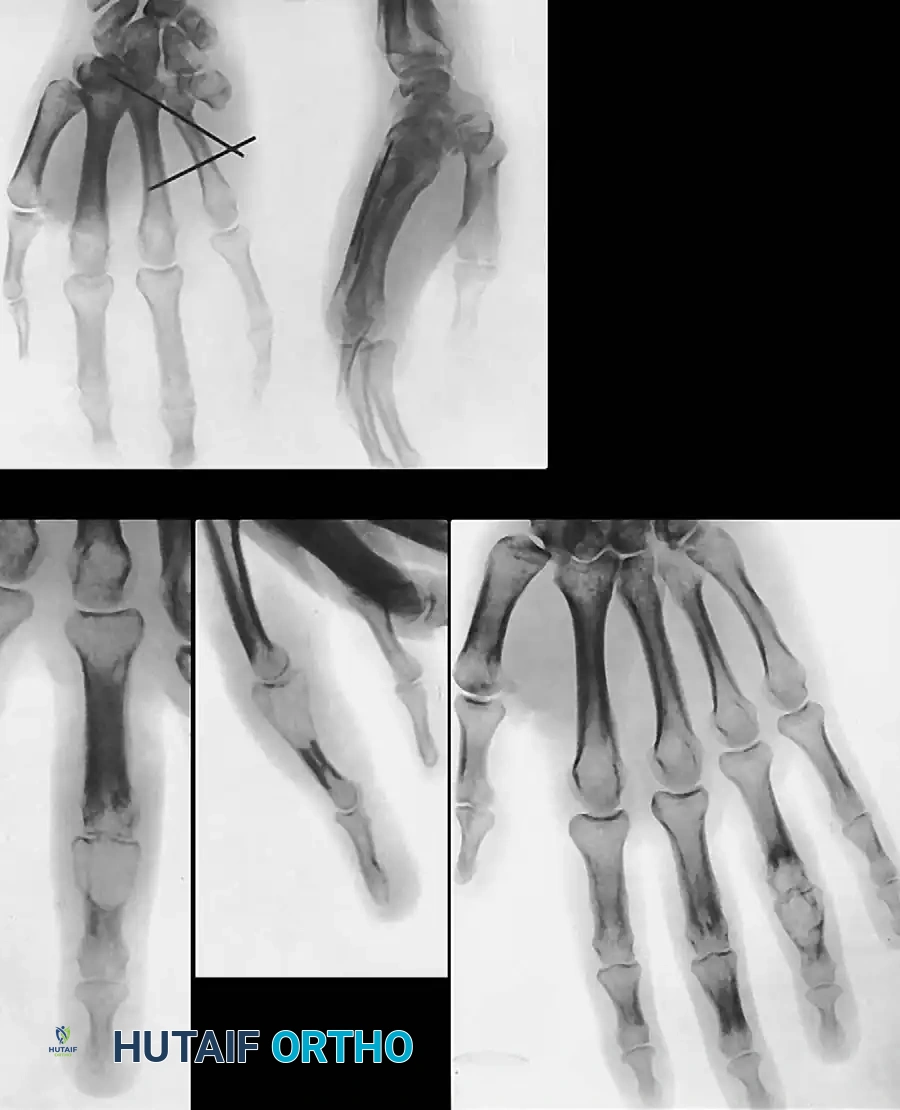

Surgical Excision and Recurrence

Excision is notoriously difficult. These tumors frequently wind in and around the flexor tendons, their synovial sheaths, digital nerves, and occasionally the extensor mechanism, sometimes encompassing three-fourths of

Associated Surgical & Radiographic Imaging

Hutaifortho's Orthopaedic Diagram